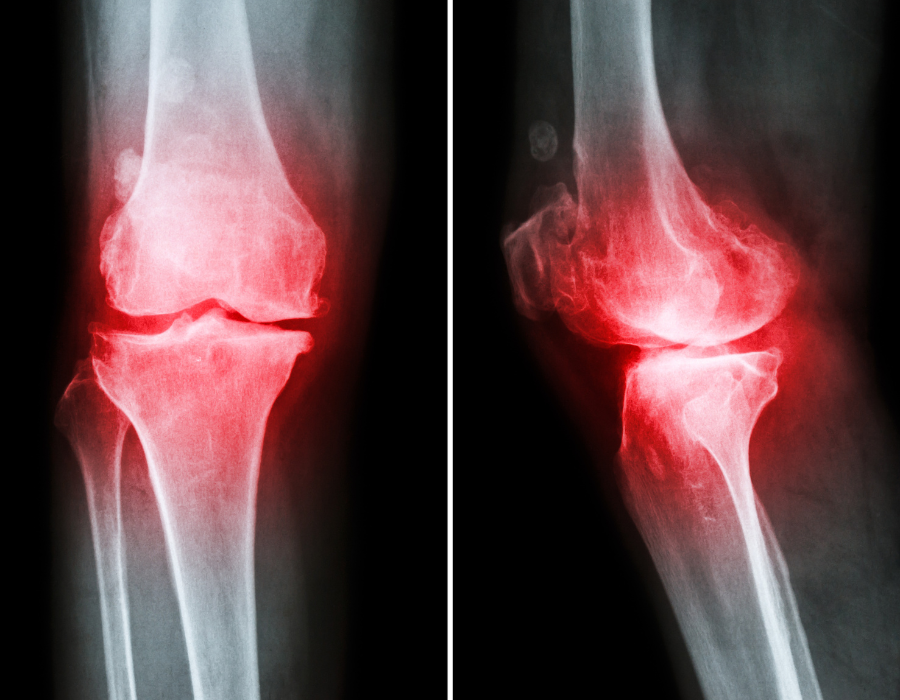

Thoái hóa XƯƠNG khớp thực chất là quá trình lão hóa của cơ thể, khiến cho các đầu sụn khớp bị bào mòn, nứt vỡ, thậm chí biến mất ở giai đoạn nặng, hậu quả khiến cho 2 đầu xương va chạm trực tiếp vào nhau. Thoái hóa khớp ở giai đoạn nặng sẽ gây viêm tại khớp, hậu quả là khớp sưng nóng và đau nhiều hơn.

Nhìn chung viêm xương khớp là bệnh lý xuất hiện phổ biến ở mọi lứa tuổi. Bệnh có thể ảnh hưởng tới bất kỳ khớp nào trên cơ thể nhưng thường xảy ra nhất ở khớp gối, hông, lưng, cổ,… Bên cạnh đó, bệnh gây ra nhiều biến chứng nguy hiểm khác như thoái hóa khớp, bại liệt, mất hoàn toàn khả năng vận động,…